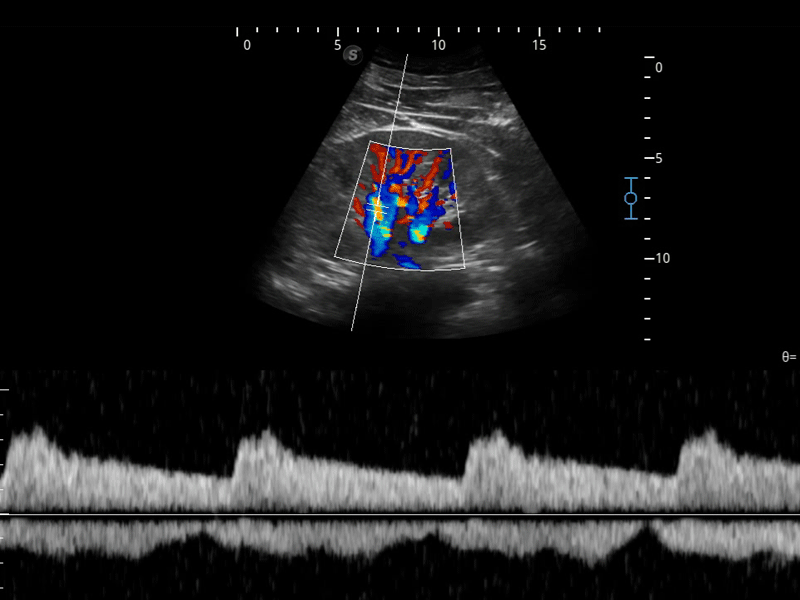

SR Flow高分辨率血流成像

高分辨率血流成像技术提高了对低速血流信号的检测能力。在提高空间分辨率的同时,也克服了血流外溢现象,为用户提供更加真实的血流动力学信息。

临床图像